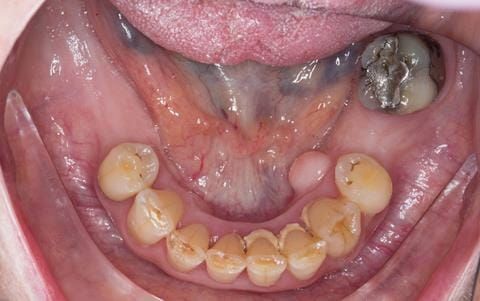

- Poorly fitting cobalt chromium based maxillary partial denture, which has been added to. This exhibited poor retention, stability and tissue fit (support). Unable to wear a new acrylic based denture.

- UR7 - occlusal amalgam. 10- 20% alveolar bone loss. Healthy periodontium with reduced attachment level. No mobility.

- Eight mandibular anterior teeth worn incisal edges from now extracted maxillary anterior crowns. Gingivitis - owing to inadequate oral hygiene.

- LL6 with large amalgam restoration - healthy periodontium.

- Bruxism.